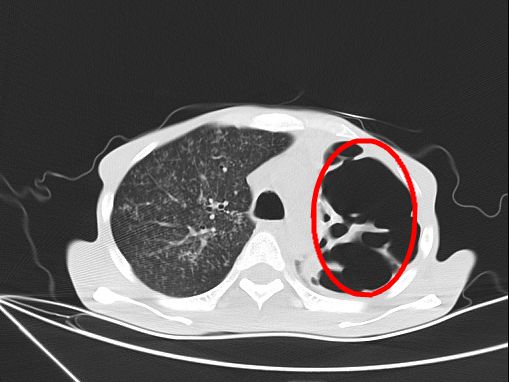

“恶病体质,瘦得皮包骨,高烧到40度,神志不清伴呼吸衰竭。”感染科主治医师张强回忆道,CT检查显示他患得是重症肺结核、肺部感染。

“通过片子看到他的左肺出现大片空洞,几乎全部消失不见,右肺大面积感染,而且有严重的贫血,随时有生命危险。”

【几乎消失不见的左肺】